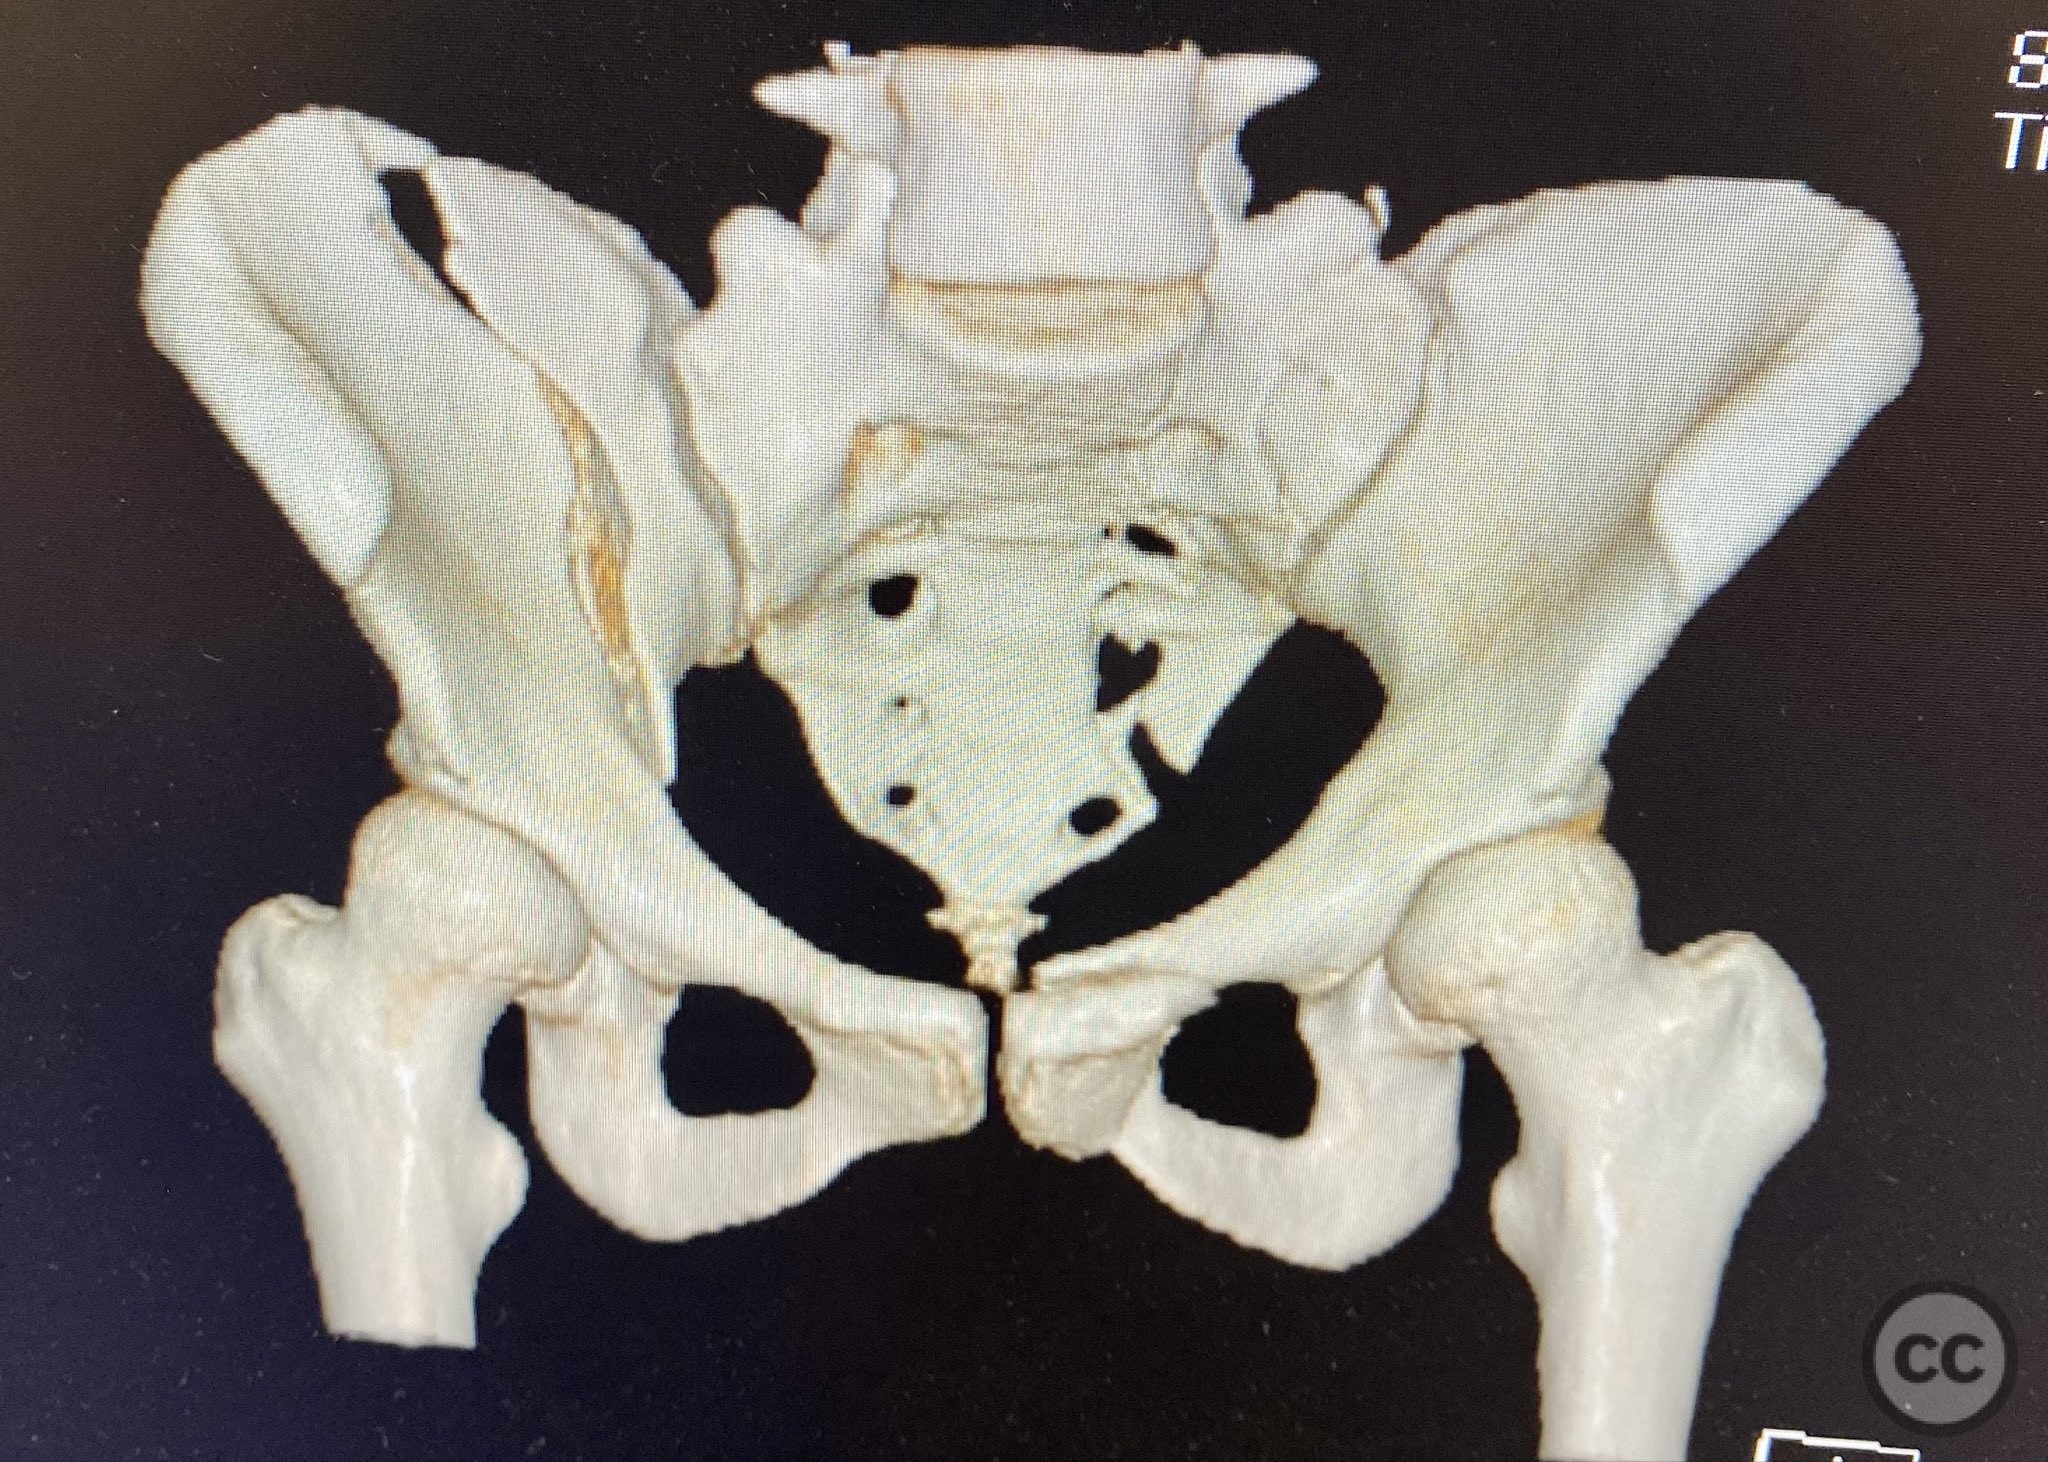

Clinical Details

Clinical and radiological findings:  The patient presented following trauma with an unusual, significantly displaced right iliac fracture, accompanied by left-sided sacral and parasymphyseal ramus fractures. Initial AP pelvic radiography demonstrated the complex injury pattern. CT imaging provided detailed characterization of the iliac and sacral fractures, including assessment of displacement, bone quality, soft tissue status, and overall body habitus. No neurovascular compromise was reported. AO/OTA classification: Right iliac fracture 61B2.3 (partial unstable, lateral compression injury), left sacral fracture Denis zone I, left parasymphyseal ramus fracture.